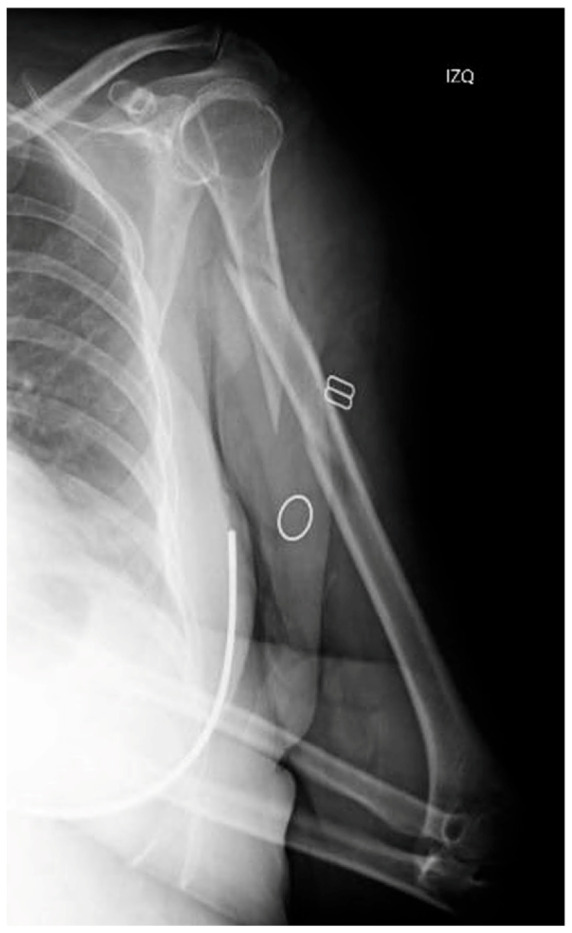

背景和临床意义:非假体种植体周围骨折(NPPIFs)是发生在内固定装置周围的罕见损伤,与假体周围骨折不同。虽然大多数研究集中在股骨,但肱骨nppif的文献记录很少。本病例说明了复杂的肱骨NPPIF,并强调了关键的手术注意事项。病例介绍:一名62岁女性在跌倒后出现螺旋状肱骨轴骨折(ao12b2)。在闭合复位和顺行髓内钉固定后,术中远端联锁螺钉发生种植体周围骨折。CT显示一复杂骨折,从外侧髁延伸至肱骨近端。治疗包括植入物移除和切开复位双钢板固定-外侧远端和螺旋形近端钢板-加上环扎带和载抗生素珠。恢复顺利,6个月时实现了全范围活动。一年后,DASH评分和MEPS分别为86分和75分。结论:肱骨nppif具有挑战性,需要个性化的、生物力学健全的策略。这个病例强调了术中评估和谨慎选择植入物在肱骨骨折治疗中的重要性。

Background and Clinical Significance: Non-prosthetic peri-implant fractures (NPPIFs) are rare injuries occurring around internal fixation devices, and are distinct from periprosthetic fractures. While most studies focus on the femur, humeral NPPIFs remain poorly documented. This case illustrates a complex humeral NPPIF and highlights key surgical considerations. Case Presentation: A 62-year-old woman presented with a spiral humeral shaft fracture (AO 12B2) after a fall. Following closed reduction and antegrade intramedullary nailing, an intraoperative peri-implant fracture occurred at the distal interlocking screw. CT imaging revealed a complex fracture extending from the lateral condyle to the proximal humerus. Treatment included implant removal and open reduction with dual plate fixation-lateral distal and helically contoured proximal plates-plus cerclage bands and antibiotic-loaded beads. Recovery was uneventful, with a full range of motion achieved at six months. At one year, the DASH score and MEPS were 86 and 75, respectively. Conclusions: Humeral NPPIFs are challenging and require individualized, biomechanically sound strategies. This case reinforces the importance of intraoperative assessment and careful implant selection in humeral fracture management.